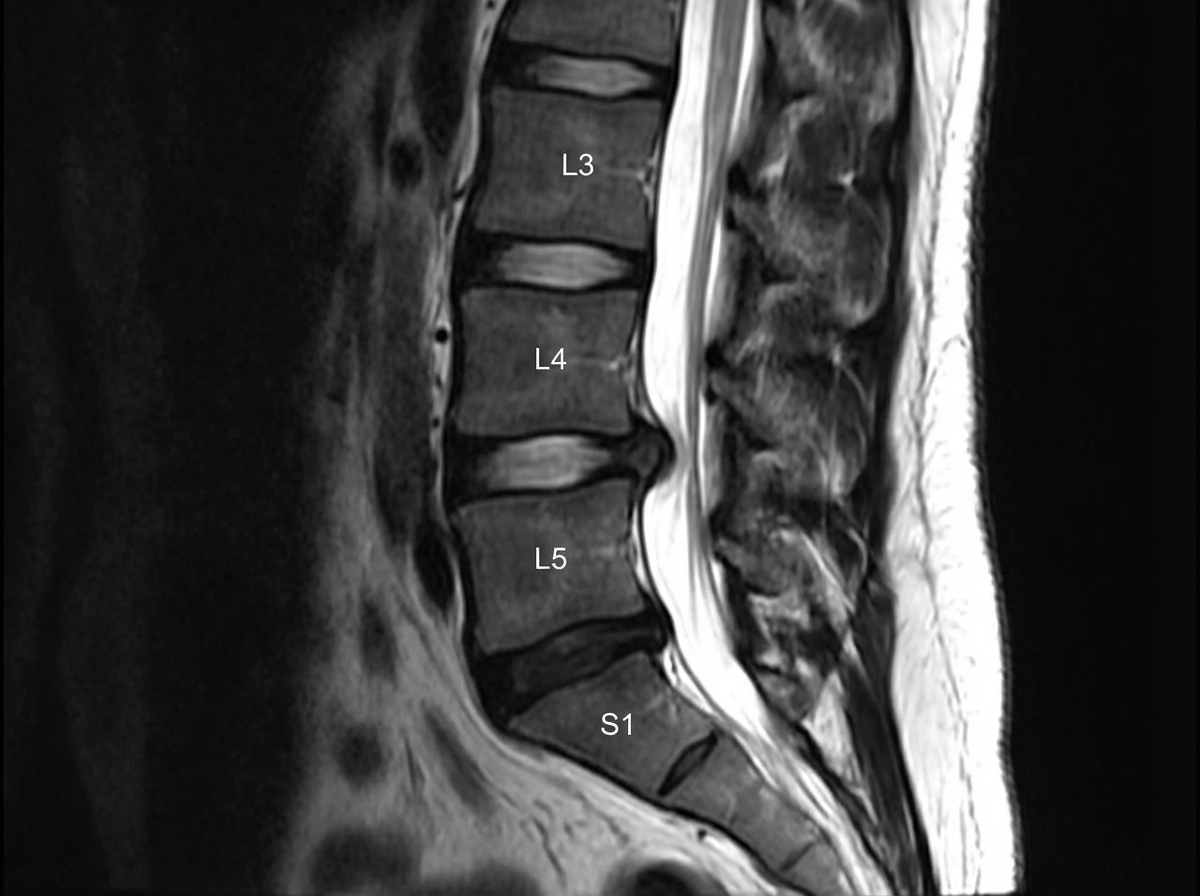

A slipped disc at the level shown in the image would most likely involve which nerve root?

Explanation: ***L5*** - The image shows a **disc herniation** at the L4-L5 level. In cases of disc herniation, it is the **nerve root exiting below the level of the disc** that is typically compressed. - For an L4-L5 disc herniation, the **L5 nerve root** is the one most commonly affected because it passes directly behind the L4 vertebral body and the L4-L5 disc before exiting the neural foramen at the L5-S1 level. *L4* - An L4 nerve root compression would typically occur with a disc herniation at the **L3-L4 level**. The L4 nerve root usually exits above the L4-L5 disc. - While sometimes L4 nerve root can be involved in a massive central L4-L5 herniation, it is less common than L5 involvement for a typical posterolateral herniation at this level. *S1* - The S1 nerve root would be involved in a **disc herniation at the L5-S1 level**, as it exits below the L5-S1 disc. - The disc herniation visible in the image is clearly above the L5-S1 intervertebral space. *L3* - Compression of the L3 nerve root usually results from a disc herniation at the **L2-L3 level**, which is higher than the level depicted in the image. - The L3 nerve root is anatomically shielded from an L4-L5 disc herniation. *L2* - The L2 nerve root would be affected by a disc herniation at the **L1-L2 level**, which is significantly higher than the level shown in the image. - L2 nerve root involvement would present with different clinical features (primarily hip flexion weakness and sensory changes in the anterior thigh).